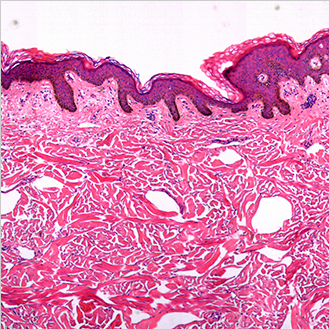

TM-Microscopy

Cette solution permet d’optimiser la diffusion et l'accès des images d’anatomo-pathologie, par la récupération, le stockage et la mise à disposition des images au sein du viewer TM-Microscopy. Il assure un diagnostic de grande qualité grâce à une meilleure pertinence du diagnostic des échantillons et un échange amélioré entre pathologistes. En savoir plus?